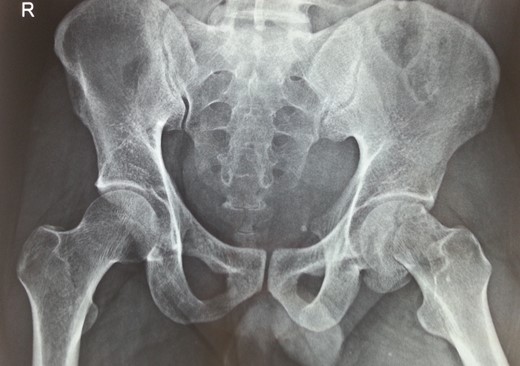

Following trauma patient had left-sided chest pain, frontal headache and severe pain in his left hip region. After hemodynamic stabilization and preliminary treatment for his chest and head injuries, he was evaluated for left hip region pain. Clinically patient had left anterior hip joint line tenderness. Initial X-ray imaging showed impacted subcapital fracture of femur neck, with varus angulation between femur head and neck (Fig. 1), which prompted detailed radiological evaluation. A 3D reconstructed CT scan imaging disclosed a separate fracture line in femur head, with a detached inferior head fragment (Fig. 2); thus, the patient had concurrent ipsilateral fracture of femur head and neck without hip dislocation. We decided to treat this fracture pattern surgically with either osteosynthesis and fixation, or primary total hip arthroplasty. Via posterolateral approach to hip, femur head and neck fractures were exposed. Proximal femur fragment showed severe impaction of cancellous bone, making chances femur head salvage with osteosynthesis precarious. Thus, we performed primary uncemented total hip arthroplasty (Fig. 3). Presently, the patient is 5 years post-surgery without any complaints and ambulates without support or limp.

Antero-posterior radiograph showing subcapital fracture line of left femur neck.